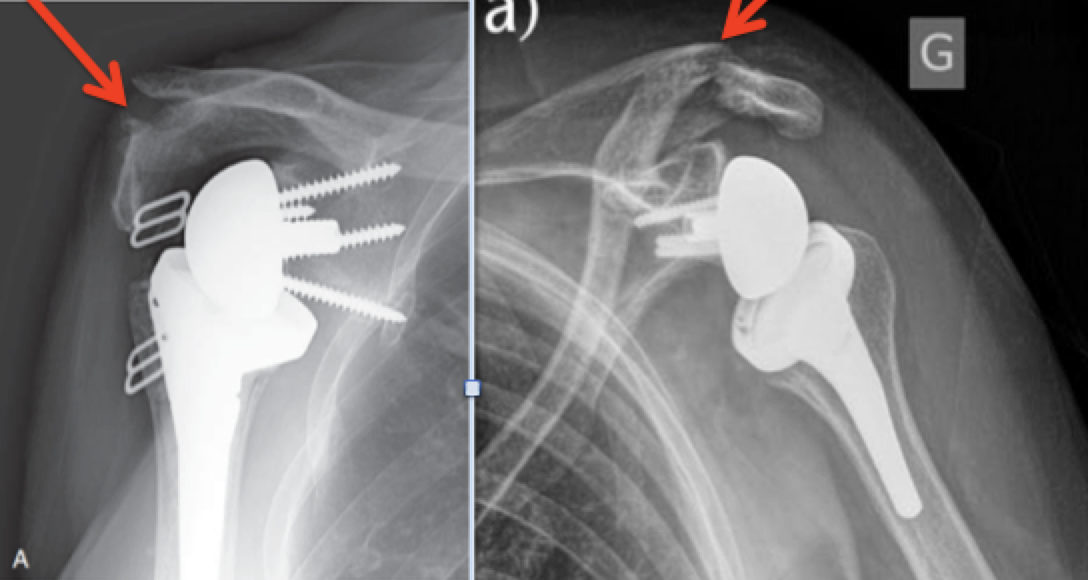

A 2years followup Xray for an outpatient reverse total shoulder Is Reverse Shoulder Replacement Outpatient The ball is attached to the shoulder. In many cases, the surgery is performed on an outpatient. In the reverse total shoulder replacement, the joint is literally reversed meaning the metal ball is placed where the glenoid. in a patient with a large rotator cuff tear and cuff tear arthropathy, these muscles no longer function. Both the ball and. Is Reverse Shoulder Replacement Outpatient.